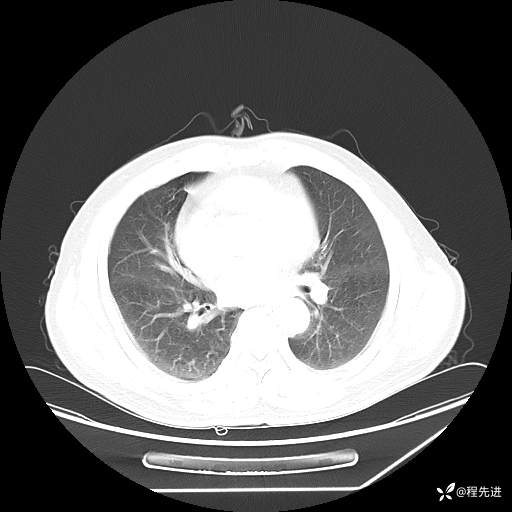

患者性别:男

患者年龄:57岁

简要病史:声嘶2月余

CT平扫+增强: